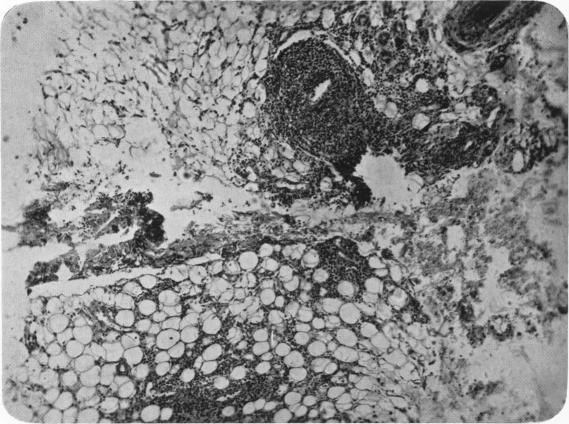

A case of periarteritis nodosa with subcutaneous lesions and recovery.

Arch Dis Child. 1938 Mar;13(73):31-44. doi: 10.1136/adc.13.73.31.